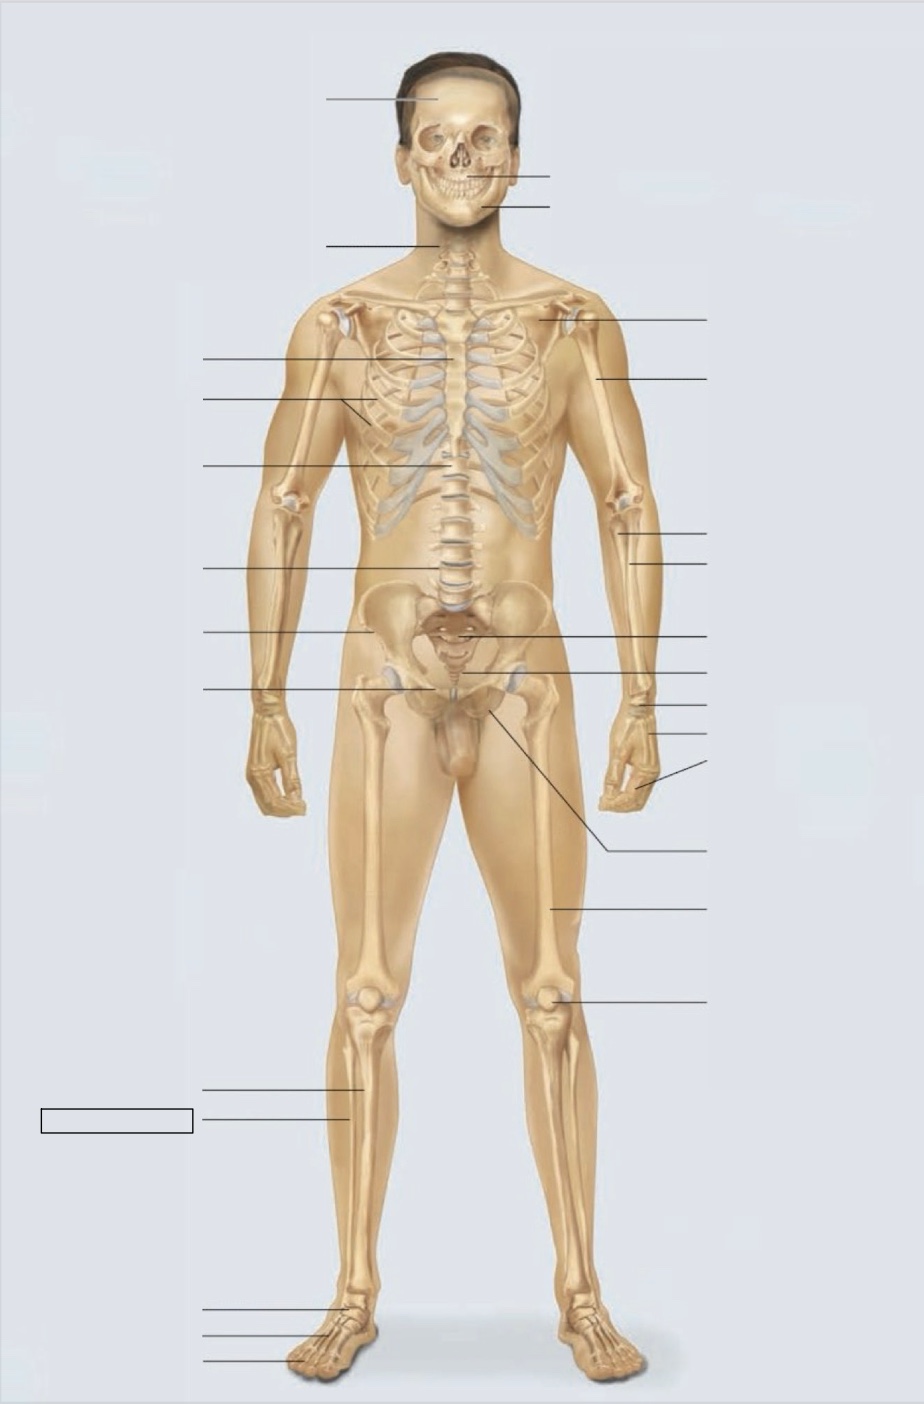

maxilla

mandible

scapula

humerus

ulna

radius

sacrum

coccyx

carpals

metacarpals

phalanges

ischium

femur

patella

phalanges

metatarsals

tarsals

fibula

tibia

pubis

ilium

lumbar vertebrae (L4)

thoracic vertebrae (T11)

ribs

sternum

cervical vertebrae

skull